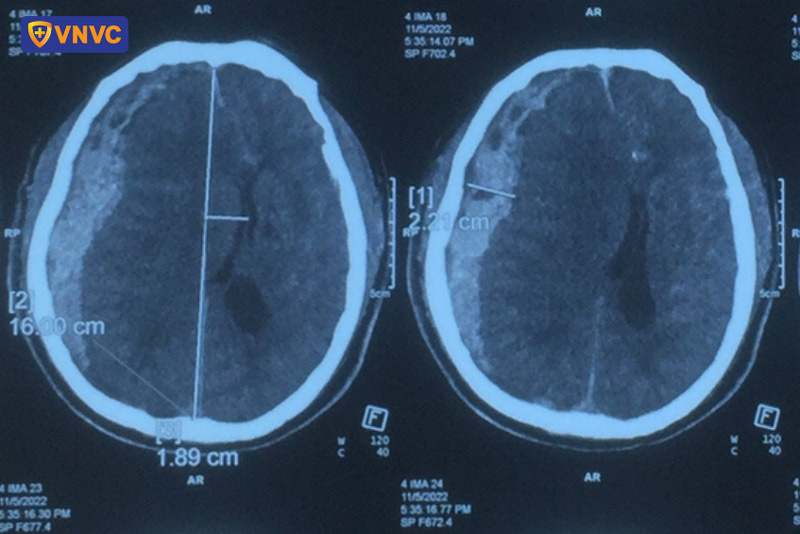

5. Xuất huyết não

Xuất huyết não là một trong số biến chứng xuất huyết đặc biệt nguy hiểm. Xuất huyết não khó nhận biết vì biểu hiện ban đầu không rõ ràng nhưng lại tiến triển nhanh, dễ gây tử vong. Ban đầu, người bệnh sốt, đau đầu, buồn nôn, sau đó tay chân dần tê liệt không cử động được. Cuối cùng, người bệnh rơi vào trạng thái hôn mê, dẫn đến tử vong. Ở người lớn, khi mắc bệnh sốt xuất huyết, tỷ lệ xuất huyết não chiếm 1%, máu chảy lan nhiều chỗ trong não. Đây là nguyên nhân chính gây tử vong cao ở người lớn khi mắc bệnh này.